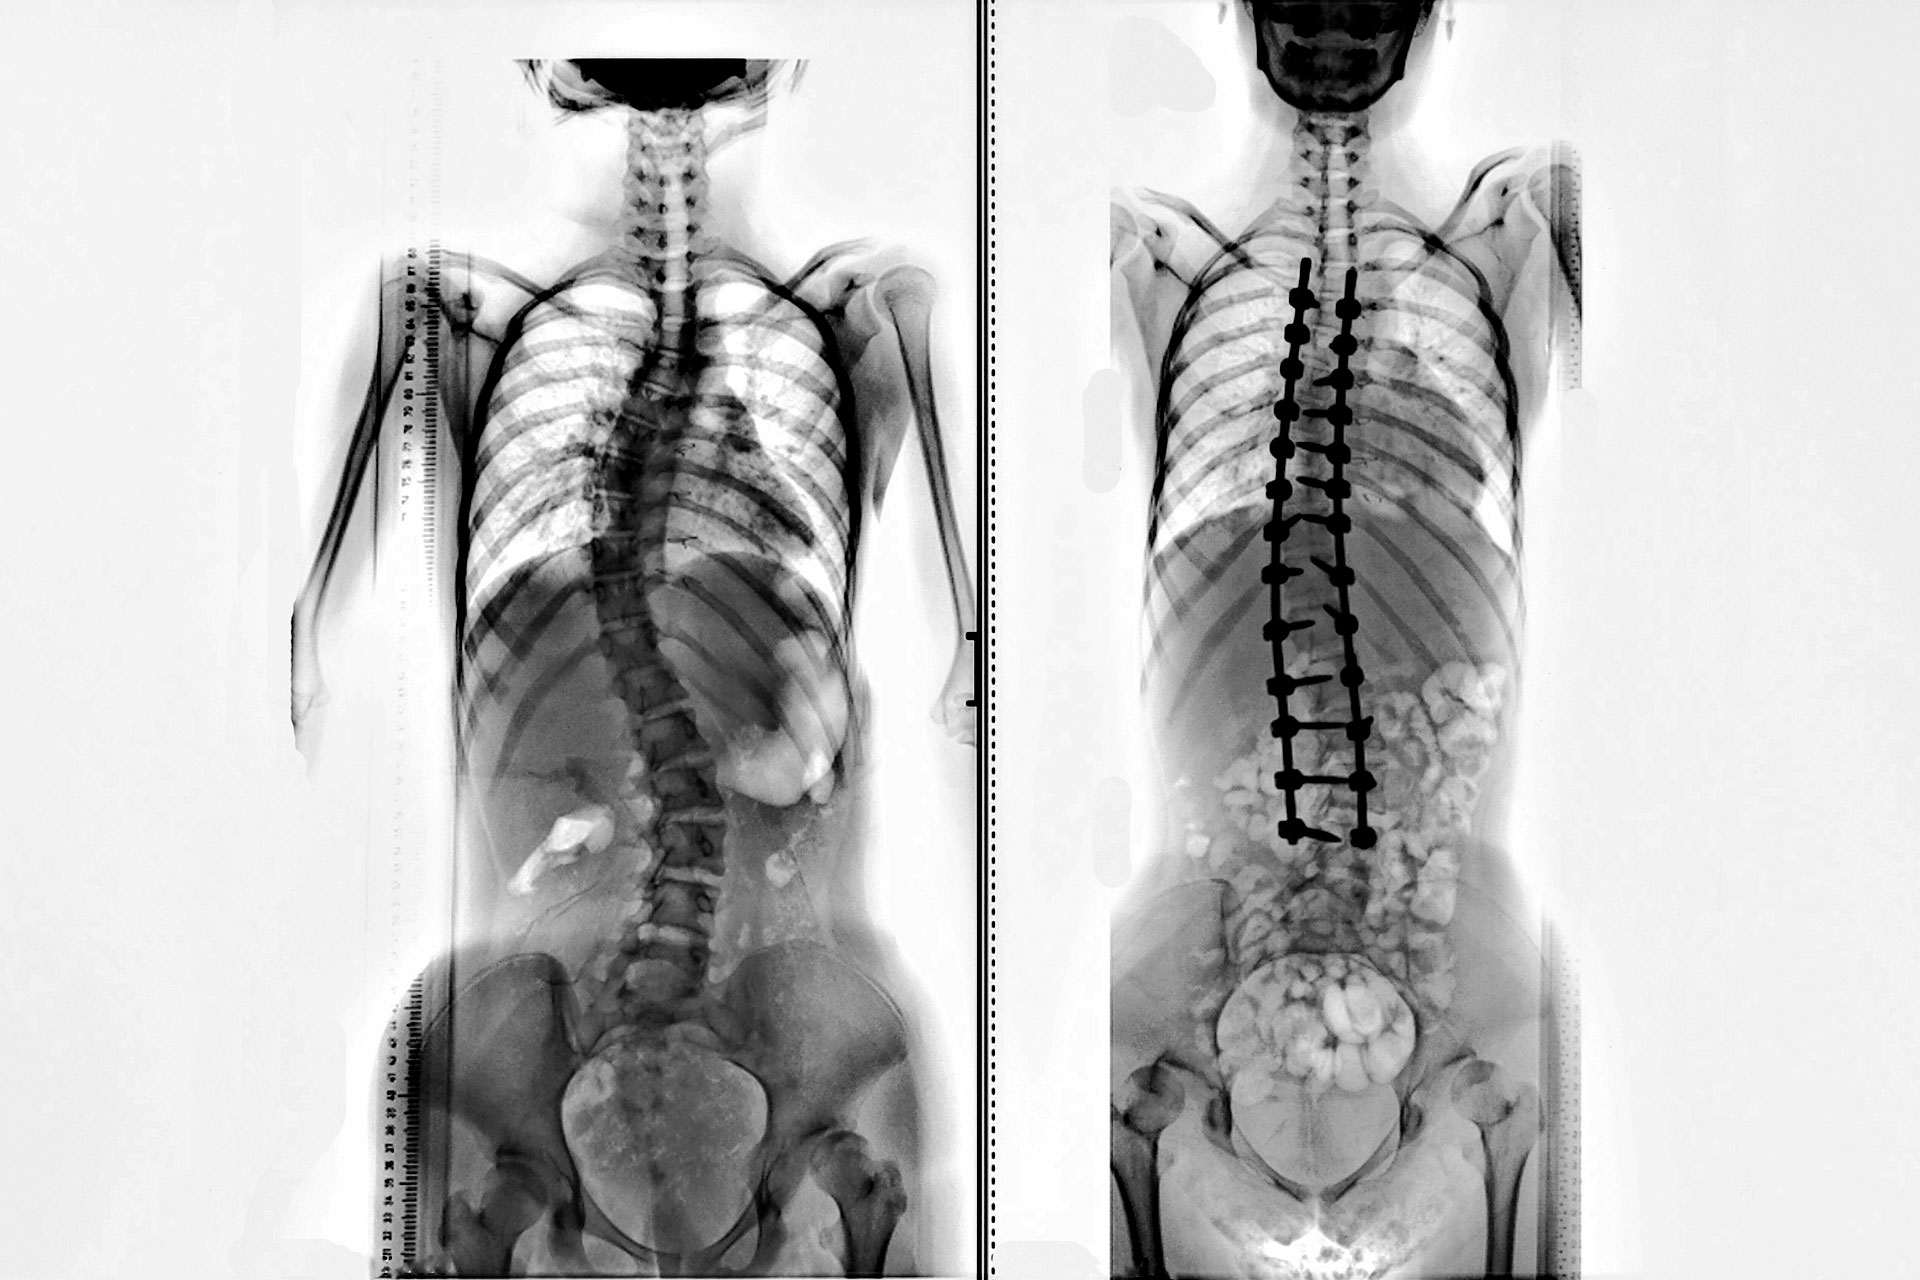

Adult and Pediatric Scoliosis Reconstruction

Scoliosis is when there is a significant curvature in the spine. It often happens in those with neuromuscular conditions or for many the cause is Idiopathic (unknown cause). Scoliosis is often diagnosed in adolescence and has an incidence of 1/1000, affecting females more often than males. While it may start out as a mild, it's very possible that scoliosis can worsen over time and cause issues throughout life if untreated. It's important to measure the curves early and watch for progression to avoid any complications that can occur due to severe scoliosis.

If scoliosis is severe, your doctor may recommend surgery to deal w ith the curve. This could be through spinal fusion, where your doctor w ill fuse together vertebrae in the spine to help hold the spine straight.

Another form of surgery is with an expanding rod. This is usually suggested for children who have rapidly developing scoliosis and the rod can be lengthened every 3 to 6 months.